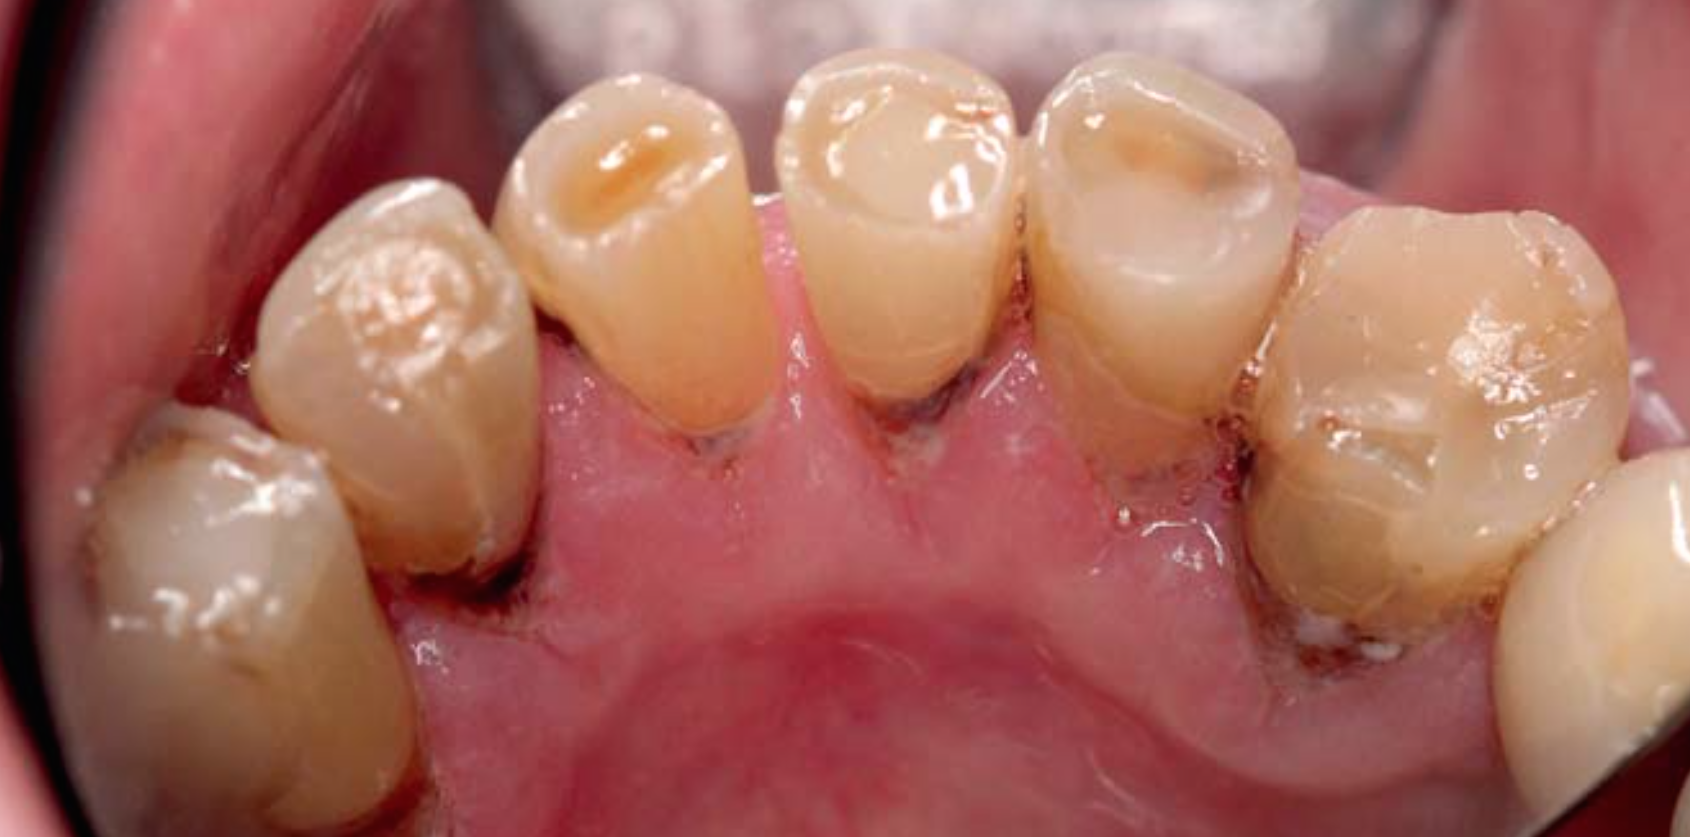

Prävention von Wurzelkaries bei älteren Patienten

Die Prävention von Wurzelkaries ist insbesondere bei Senioren wichtig. Bei der intraoralen Untersuchung von älteren Patienten ist auf Hinweise für ein erhöhtes Kariesrisiko, z. B. Mundtrockenheit, zu achten. Das Wurzelkariesrisiko sollte durch Beeinflussung von Risikofaktoren gesenkt und das Neuauftreten oder das Voranschreiten von Wurzelkaries mit kariespräventiv wirksamen Substanzen reduziert werden.

Die Zähne von Senioren unterliegen aufgrund von altersbedingten Veränderungen einem hohen Risiko für die Entstehung von Wurzelkaries. Die restaurative Versorgung von Wurzelkaries ist oft nur eingeschränkt durchführbar: Häufig liegen die Läsionen in schwer zugänglichen Bereichen. Aufgrund von körperlichen oder geistigen Einschränkungen sind pflegebedürftige Senioren häufig nur eingeschränkt behandelbar. Daher besteht bei älteren Patienten ein hoher Bedarf an effektiven und zugleich einfach durchzuführenden Präventionsmaßnahmen. Neben der Beeinflussung von Ernährung, Mundhygiene oder Speichelfluss sollten zusätzlich kariespräventiv wirksame Substanzen eingesetzt werden. Tägliches Zähneputzen mit einer Zahnpasta mit einem Fluoridgehalt von 5.000 ppm oder die Applikation von Silberdiaminfluorid, Chlorhexidin- oder Fluoridlack scheinen die Entstehung oder das Voranschreiten von Wurzelkaries zu reduzieren. Die Evidenz zur Wirksamkeit dieser Maßnahmen basiert jedoch nur auf wenigen klinischen Untersuchungen.